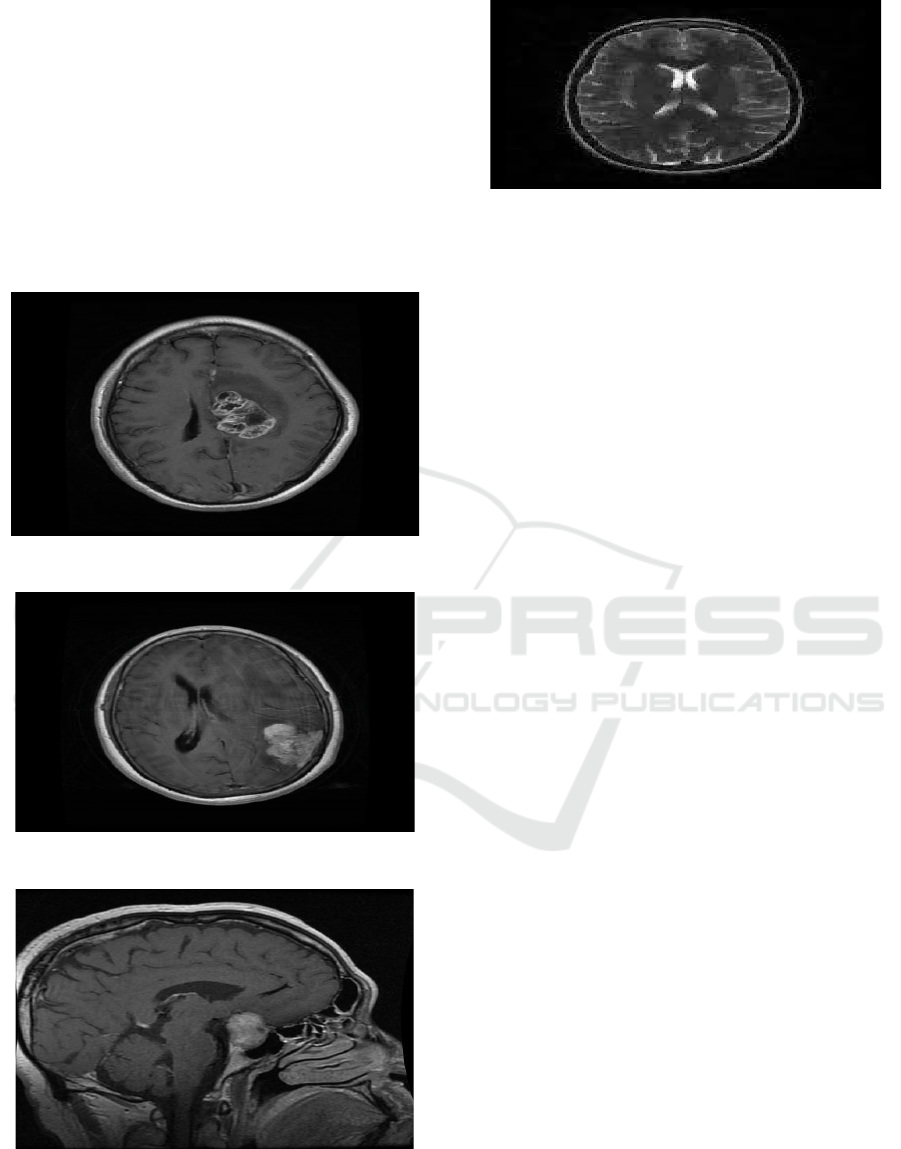

decision support. Figure 2 shows the MRI brain

images used for the proposed system.

Figure 2: MRI brain images.

Figure 3 to 6. The results in Figure 3 shows that if a

tumor is present and the type of brain tumor identified

is glioma. It should also contain a suggestion like

The MRI scan confirms the presence of a

meningioma tumor in Figure 4. It would be best to

check in with a neurologist for assessment and

Figure 3: Found glioma tumor.

Figure 4: Found meningioma tumor.

Figure 5: Found pituitary tumor.

Figure 6: No tumor found.

The model has successfully detected a pituitary

tumor in the MRI scan as shown in Figure 5,

accurately segmenting the affected region and

differentiating it from healthy brain tissue. Using the

trained Fully Convolutional Network (FCN), the

system classifies the tumor based on learned features

with a high confidence score, ensuring reliability in

diagnosis. The segmentation map visually highlights

the tumor boundaries, allowing radiologists to

analyze the size, shape, and location of the

abnormality. This automated detection significantly

reduces diagnosis time, minimizes human error, and

enhances decision-making in treatment planning. The

results can be further validated through clinical

assessment, ensuring that the system provides a

robust and efficient tool for early brain tumor

detection.

The Figure in 6 depicts no tumor found in the MRI

scan. No abnormal growth on the brain or any sign.

However, the patient should continue to seek